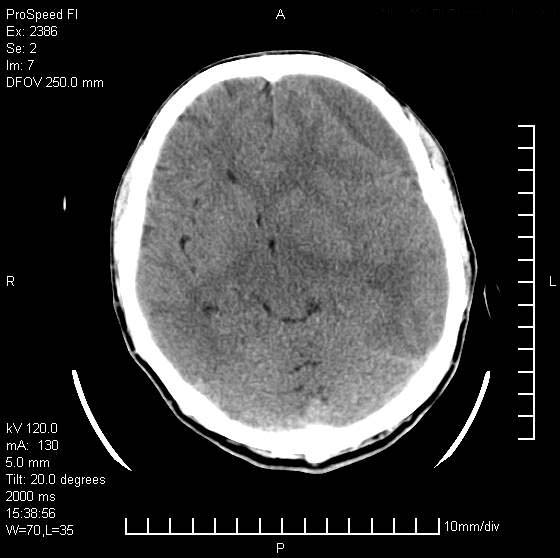

以下是引用天南地北在2007-9-19 18:43:00的发言:[br]典型慢性硬膜外血肿[br][br][本贴已被 天南地北 于 2007-9-19 18:44:11 修改过]

以下是引用曼一拍在2007-9-20 11:06:00的发言:[br]支持慢性硬膜下血肿.[br]慢性硬膜下积液:血肿有包膜,ct值稍高于脑脊液,增强可有染色。不典型者血肿可多呈梭形.是硬脑膜与蛛网膜之间的潜在腔隙内的血肿。[br]鉴别:[br]1\\硬膜外血肿:是颅脑外伤后脑膜或板障内血管破裂,血液在颅骨与硬膜之间积聚所致.通常是脑膜动脉破裂,也可因静脉窦破裂或颅骨的板障静脉出血,发生于外伤的着力部,常与颅骨骨折并存。脑膜动脉出血则急,若是板障静脉出血在则可有慢性。[br]2\\硬膜下积液:(硬膜下水瘤)[br]是由于蛛网膜破裂,脑脊液经蛛网膜破口进入硬膜下腔不能回流。或水肿阻塞而形成。[br]ct表现:颅骨内板下方新月形低密度区近似脑脊液密度;占位效应清,周围无脑水肿。[br]